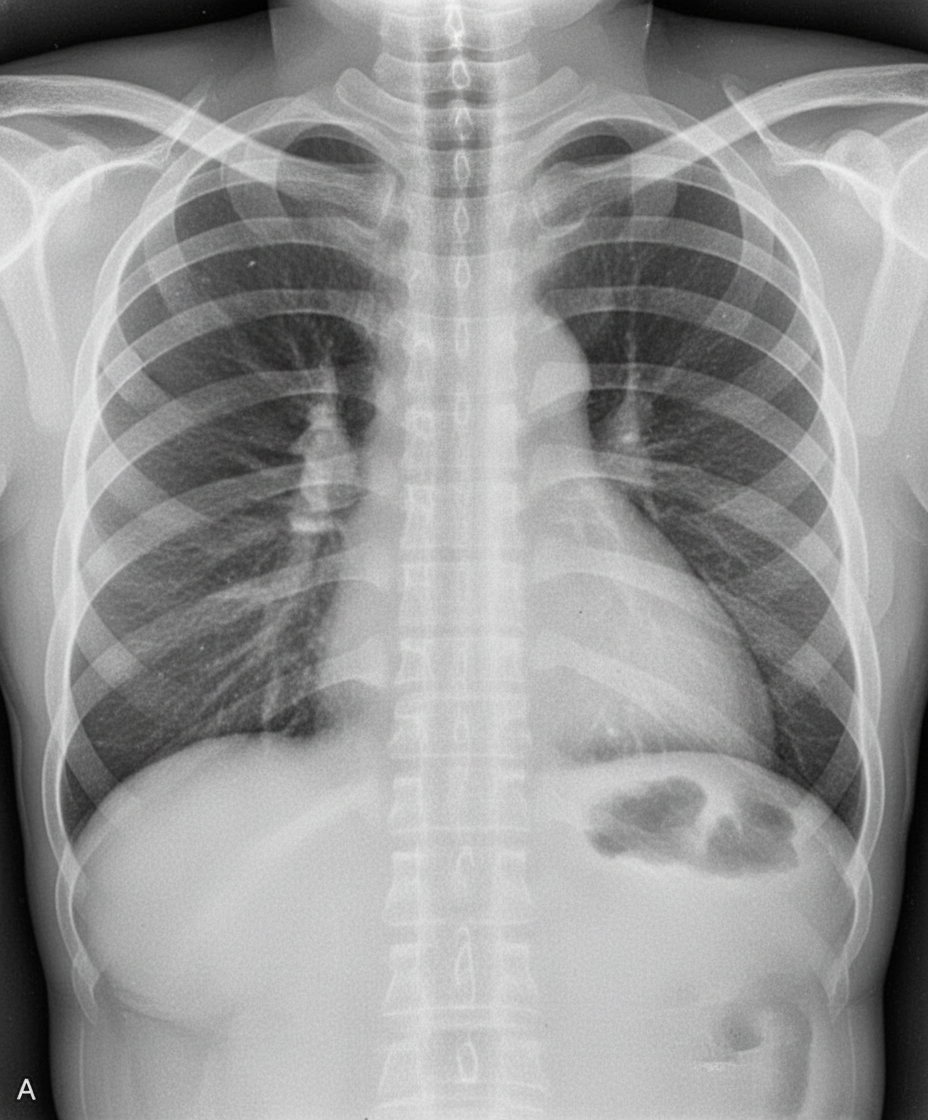

The given x-ray is suggestive of which of the following conditions?

Explanation: ***Coarctation of the aorta*** - Classic chest X-ray findings include the **figure-3 sign** (indentation of the aorta at the coarctation site) and **rib notching** due to enlarged intercostal arteries. - Shows **left heart enlargement** and **post-stenotic dilatation** of the descending aorta, creating the characteristic aortic contour. *Transposition of the great arteries (TGA)* - Chest X-ray typically shows the **egg-on-string** appearance with a narrow superior mediastinum and oval cardiac silhouette. - Often presents with **cyanosis** in neonates and lacks the distinctive aortic contour changes seen in coarctation. *Total anomalous pulmonary venous connection (TAPVC)* - Characteristic **snowman sign** or **figure-8 sign** due to enlarged superior vena cava and vertical vein creating a distinctive cardiac silhouette. - Shows **pulmonary venous congestion** and **right heart enlargement**, not the aortic arch abnormalities of coarctation. *Patent ductus arteriosus (PDA)* - Chest X-ray shows **cardiomegaly** with **pulmonary plethora** and prominent **pulmonary arteries** due to left-to-right shunting. - Lacks the specific **aortic arch deformity** and **rib notching** that are pathognomonic for coarctation of the aorta.